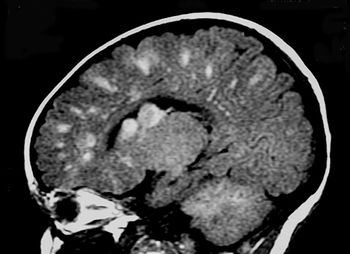

In a young patient with chronic seizures, what is the diagnosis?